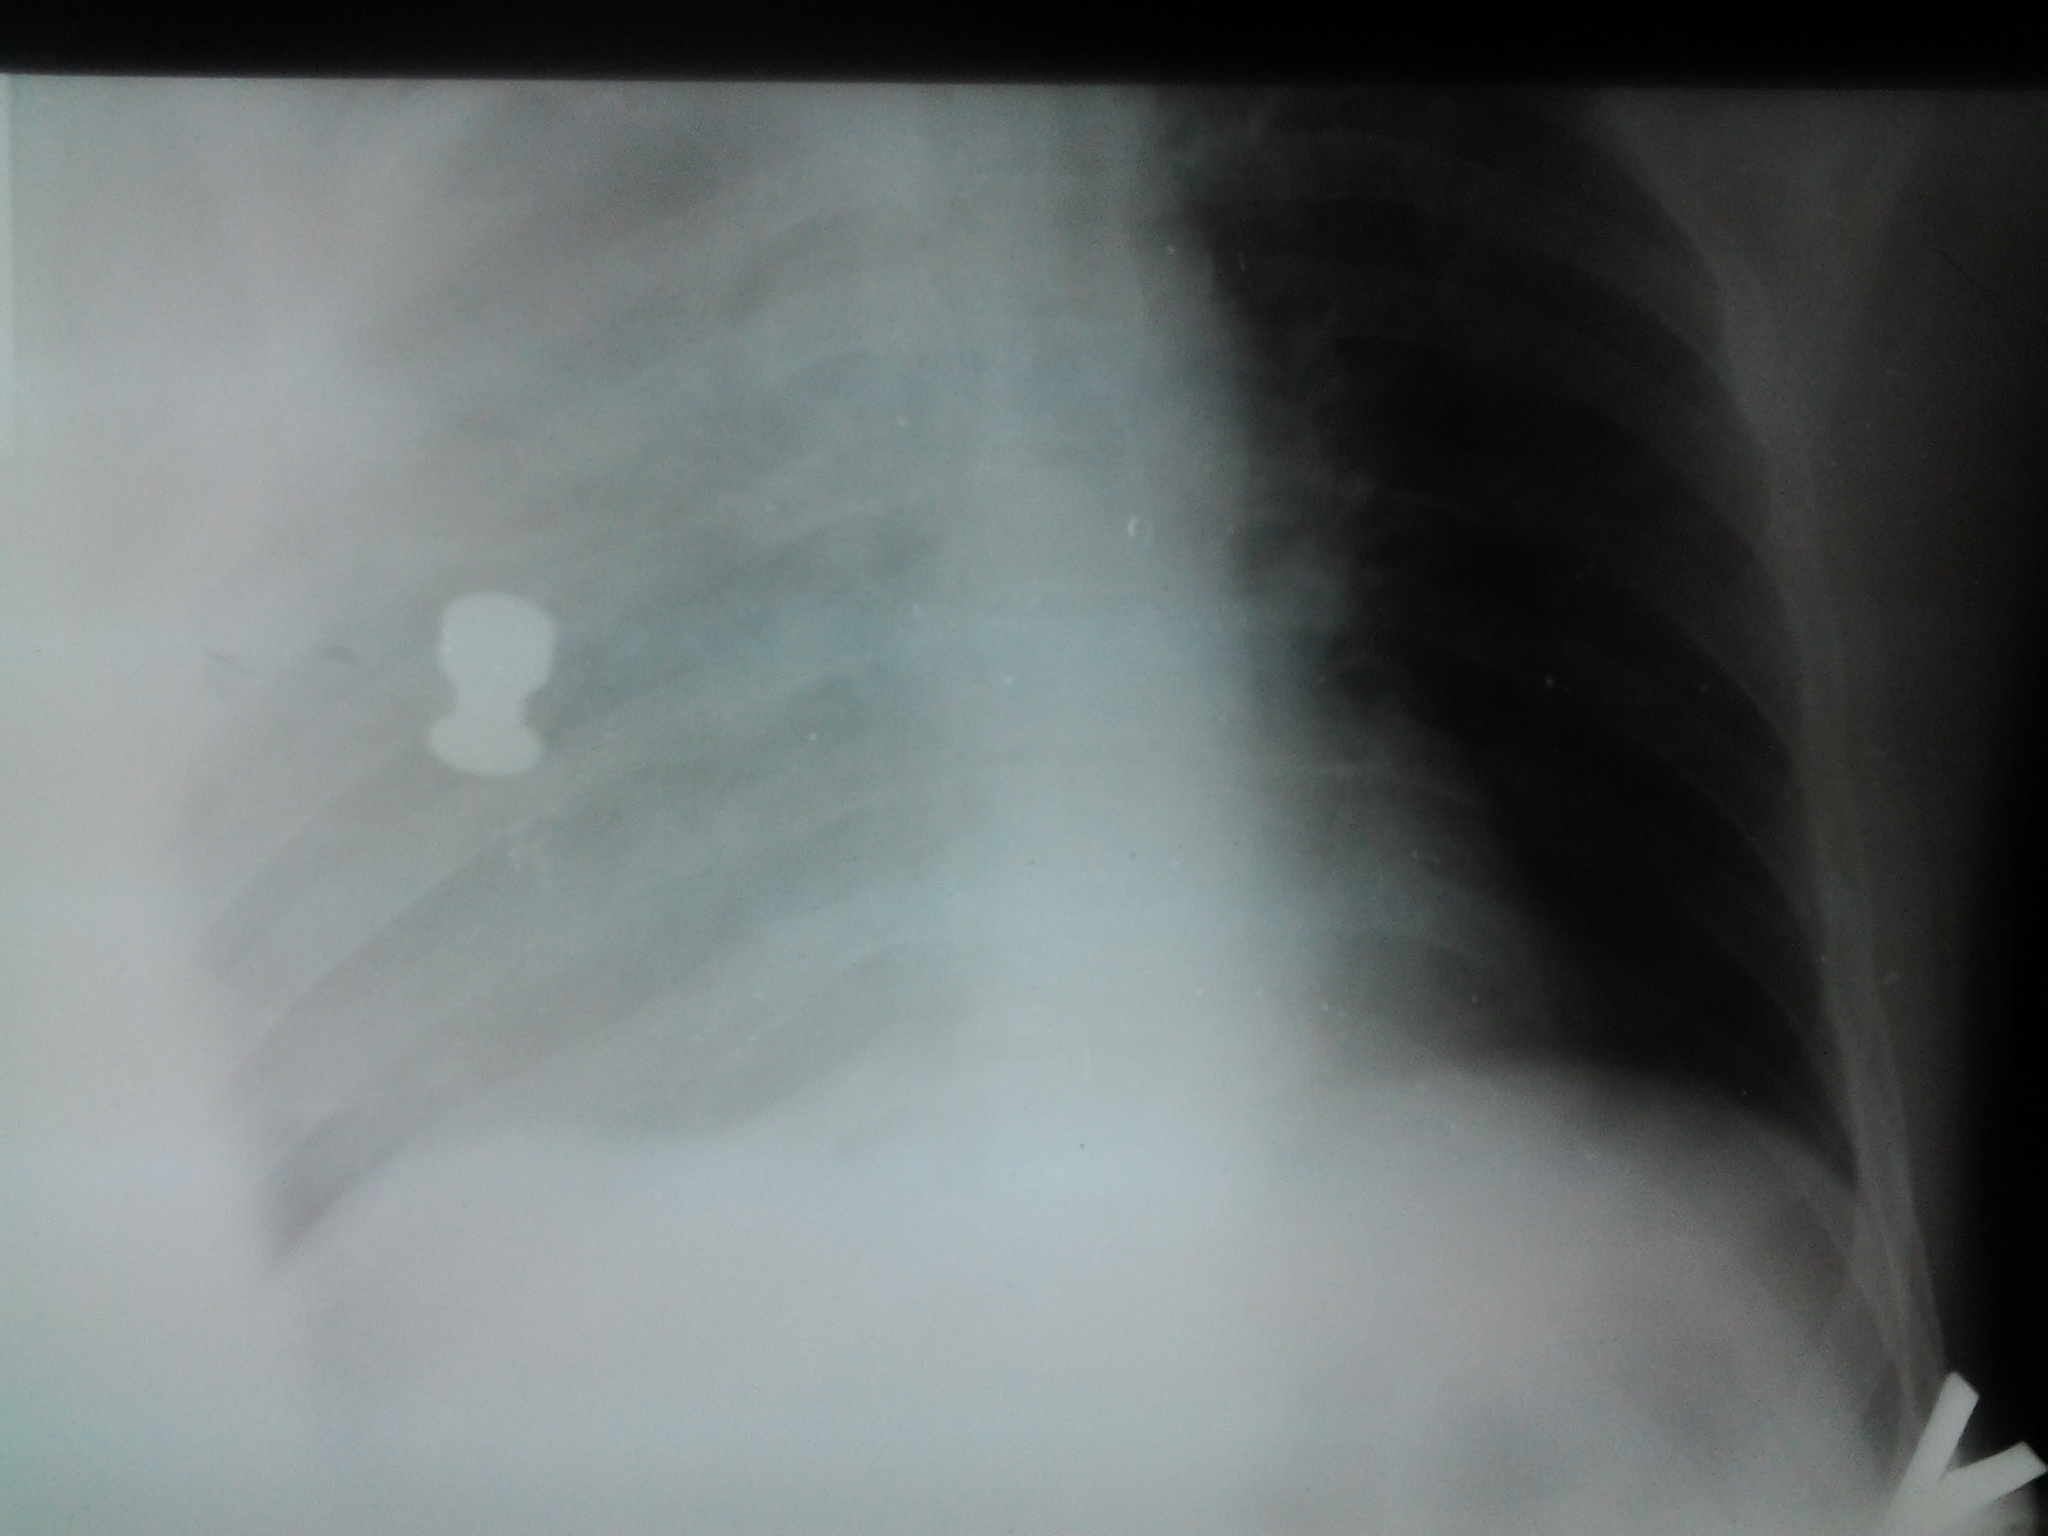

Хлопець зі Львівщини, доставлений з Грушевського, 6.

Куля Блондо, проникаюче поранення через навколоключичну область в грудну клітку зправа.

Крововтрата порядка 3 л.

Стан вкрай тяжкий...